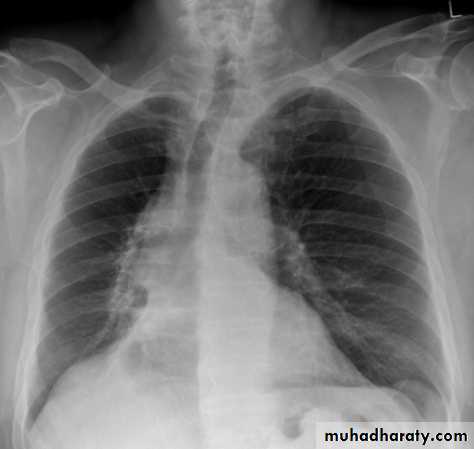

Bronchopneumonia

chest X-ray

Bronchopneumonia (also sometimes known as lobular pneumonia ) is a radiological pattern associated with suppurative peribronchiolar inflammation and subsequent patchy consolidation of one or more secondary lobules of a lung in response to a bacterial pneumonia.